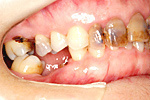

① 上の顎・治療前

② 前から見た状態・治療前